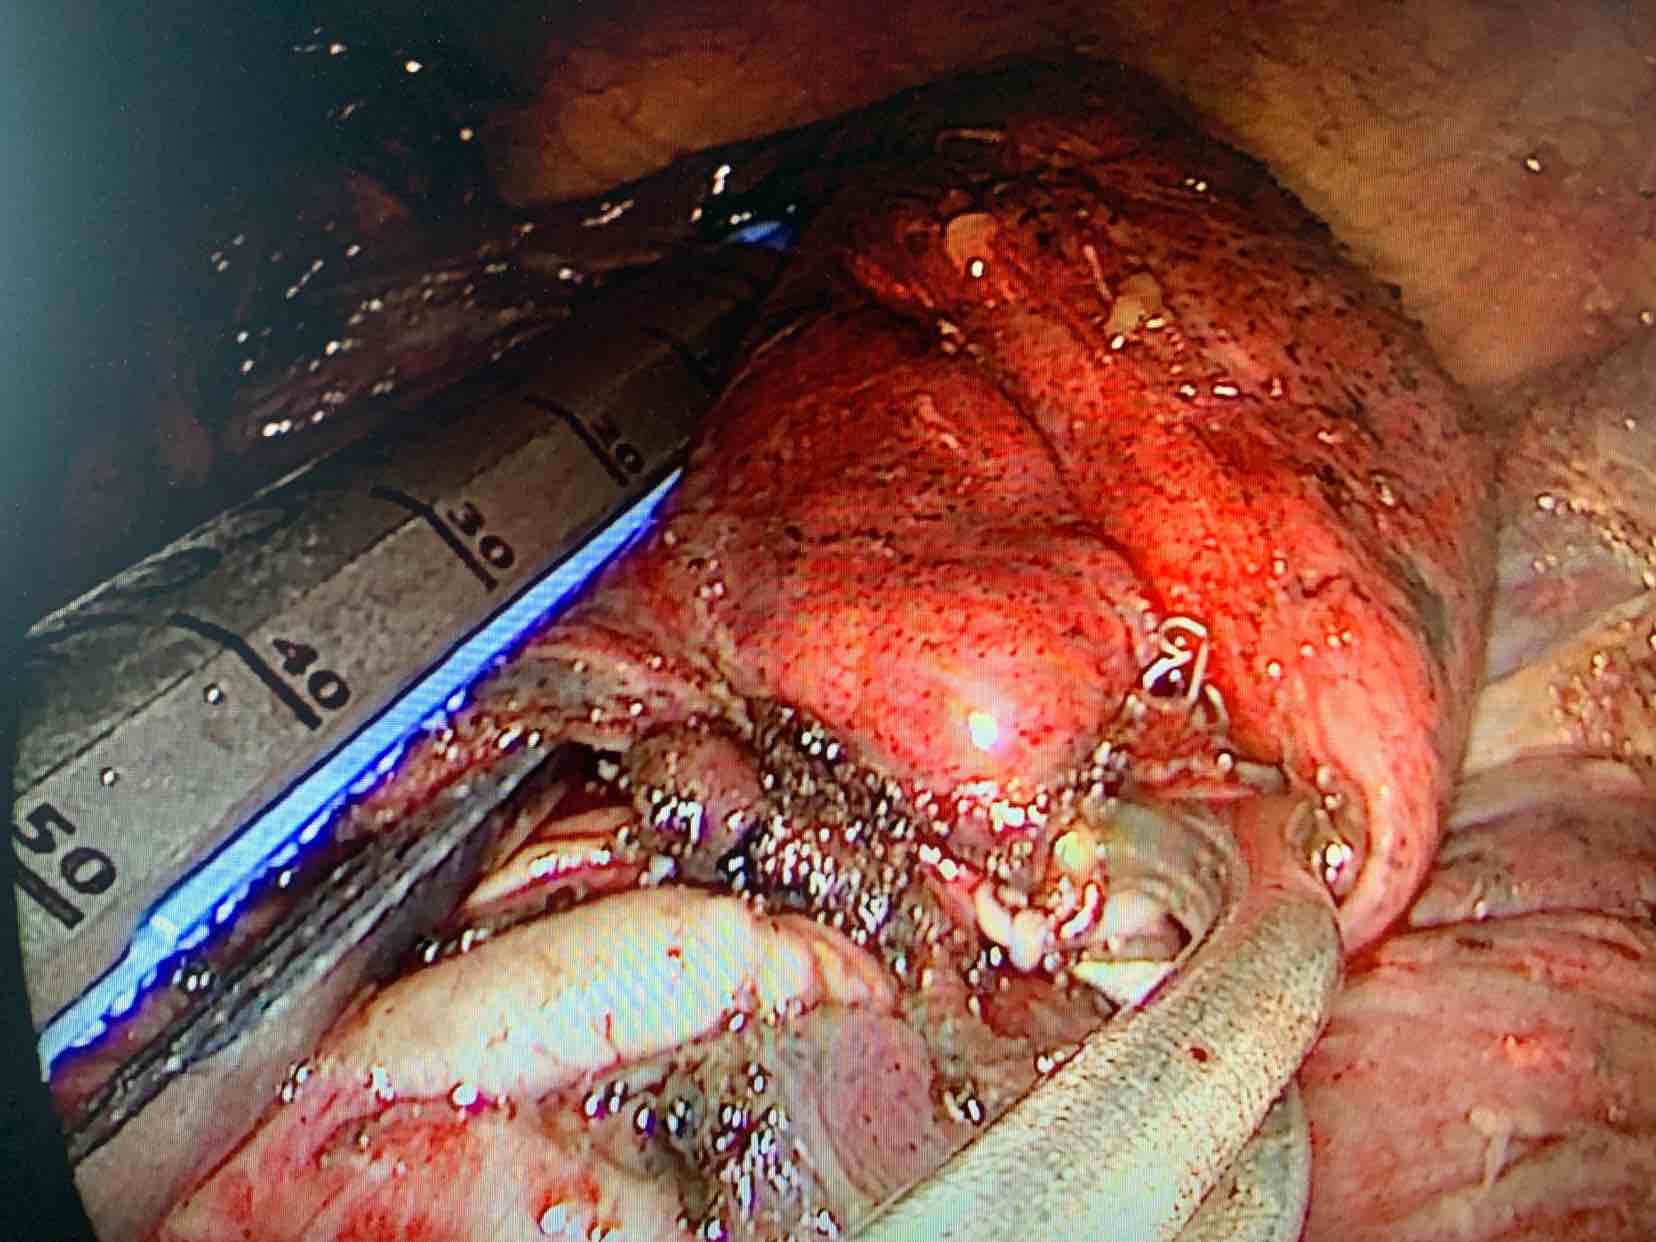

昨天用我自己创新的技术——动脉归属法 做了一台双肺深部结节手术,用一个3厘米的孔洞为患者同时切除了两个早期肺癌病灶,做到真正意义上的微创,根据结节的动脉归属行联合的亚肺段切除,非常成功效果非常好!请相信我们会做得更好,我们也一直奔跑在创新的路上! 展开>